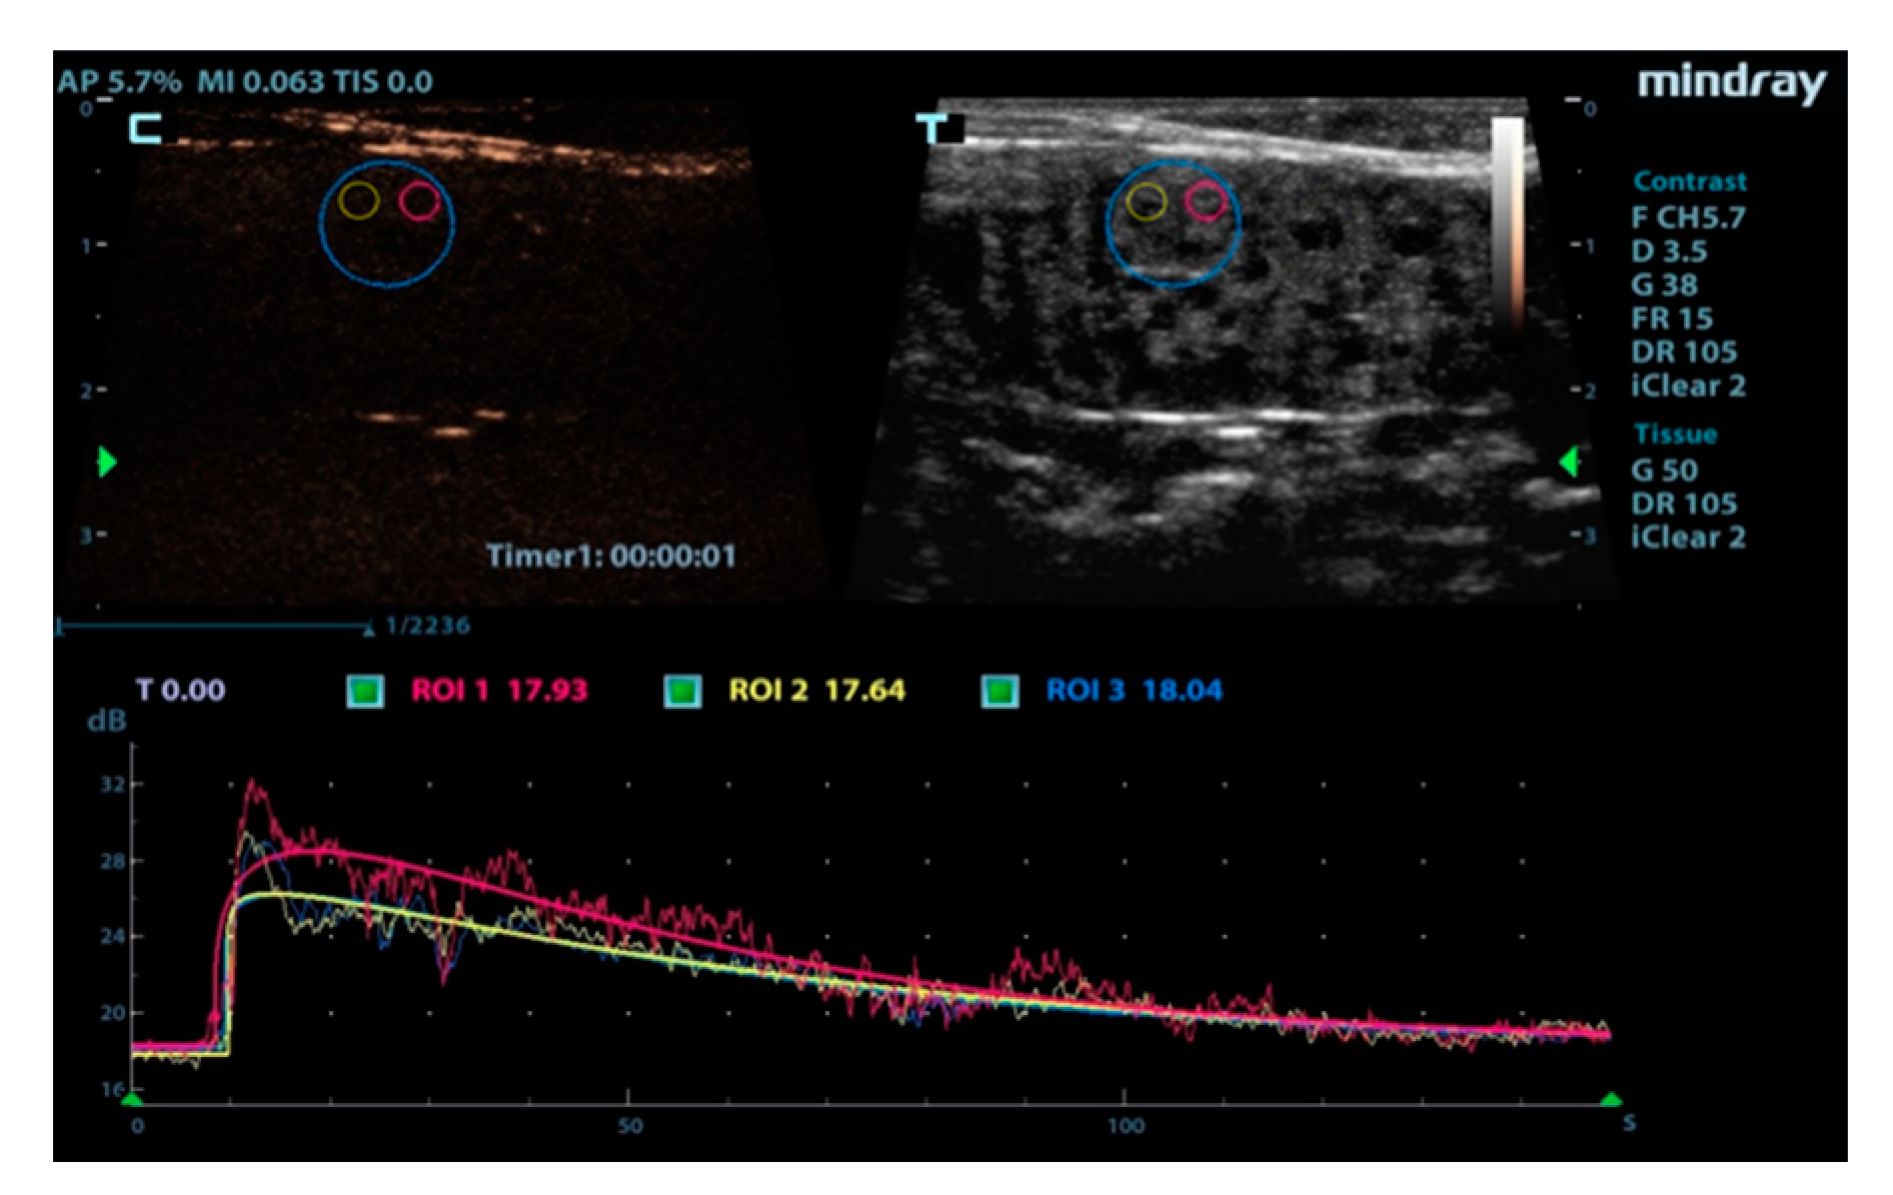

| ROI Areas | No. of Animals | GOF | BI | AT | TTP | PI | AS | DT/2 | DS | AUC |

|---|---|---|---|---|---|---|---|---|---|---|

| ROI1 | 12 | 0.93 | 18.94 | 0.13 | 6.93 | 26.46 | 0.41 | 47.26 | −0.11 | 3034.04 |

| ROI2 | 12 | 0.95 | 18.89 | 0.13 | 6.40 | 26.24 | 0.39 | 46.91 | −0.08 | 3029.55 |

| ROI3 | 12 | 0.95 | 18.11 | 0.12 | 6.62 | 26.22 | 0.46 | 47.74 | −0.09 | 3078.44 |

| SEM | 0.05 | 0.45 | 0.01 | 0.33 | 0.54 | 0.06 | 0.55 | 0.01 | 11.08 | |

| p-value | 0.32 | 0.11 | 0.41 | 0.19 | 0.15 | 0.21 | 0.33 | 0.13 | 0.09 |